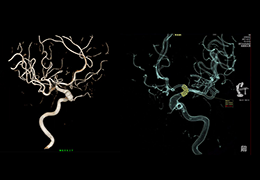

View X-Ray CT & MRI Scans Fast and Easily

Designed for surgeons, Pro Surgical 3D makes it easy to view patient scans quickly. Pro Surgical 3D facilitates the optimal 3D treatment and assessment workflows based on X-ray CT and MRI scans – and best of all, it’s FREE!

High-quality and fast 3D reconstruction and 3D rendering

Performs 3D reconstruction and volume rendering.

Multi-planar slicing.